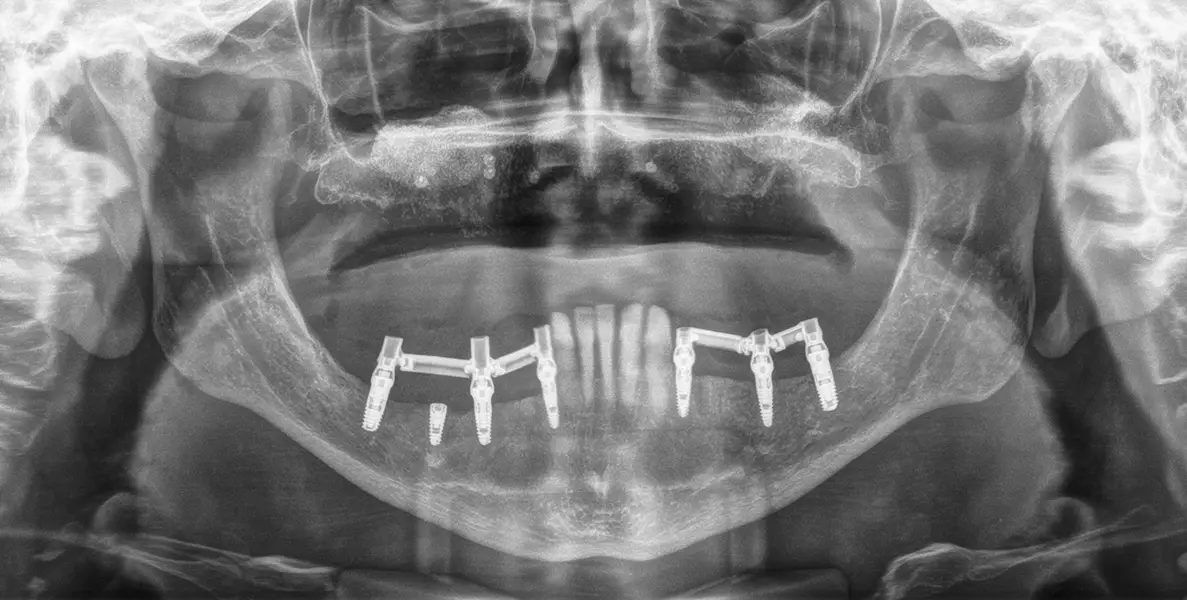

Figuras 16 y 17. Implantes colocados tras la cirugía.

Figura 18. Radiografía de la carga inmediata de 4 de los 5 implantes de diámetro reducido. Uno de ellos se deja en dos fases al presentar menor torque de inserción. Estos implantes son ferulizados a otros de mayor diámetro para la confección de la prótesis y esta se construye sobre transepiteliales, atornillada con barras articuladas horas después de la cirugía.